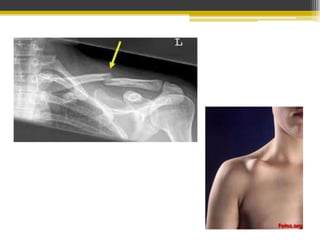

Clavícula

Omóplato